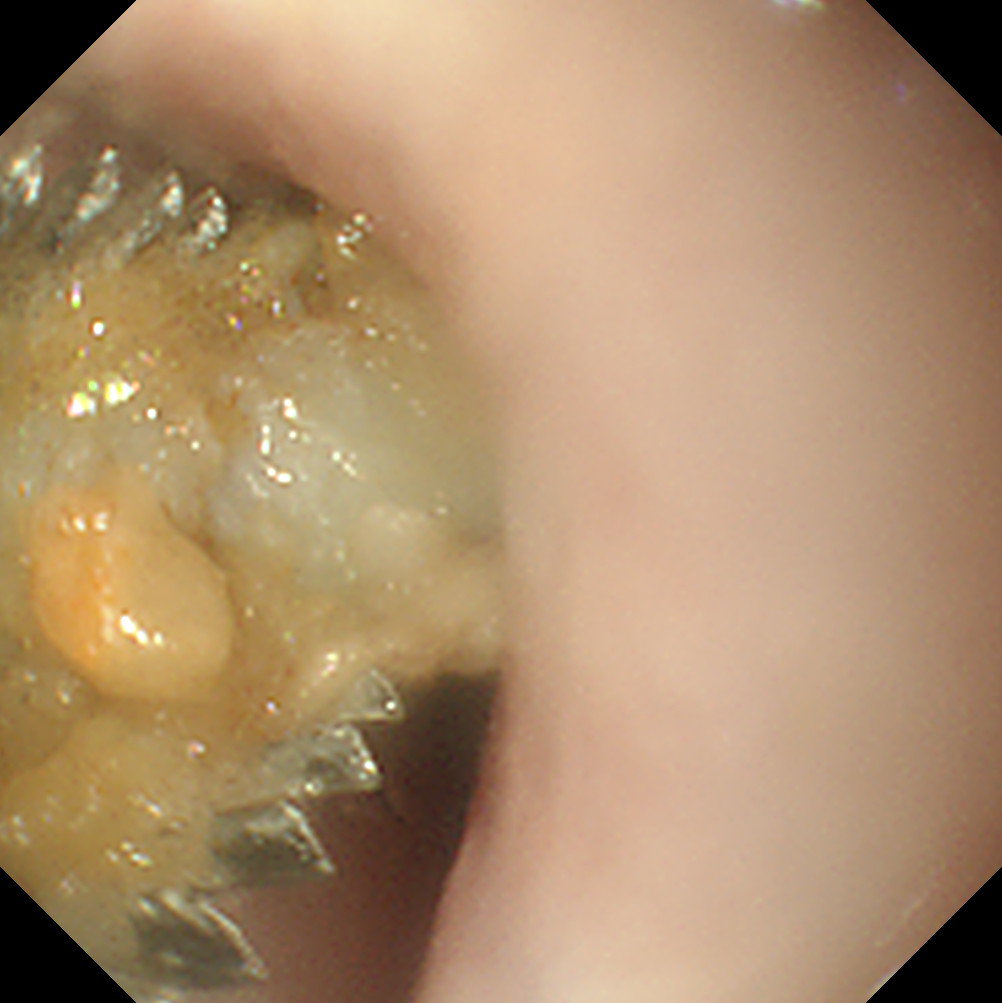

Gastric FBs

As long as grasping instruments are large enough, all except the largest and/or smoothest gastric FBs can be removed endoscopically. However, sometimes it can be frustrating chasing an object around the stomach or dropping it as one tries to pull it through the lower oesophageal sphincter. It is sensible to set a time limit on attempts at endoscopic removal of gastric FBs before opting for surgery, as a simple gastrotomy is often quicker! FBs with an edge or prominence are easier to catch with grasping forceps, whereas basket forceps or a Roth net is better for smooth/round objects.

The biggest frustration with the endoscopic removal of gastric FBs is that the FB often falls out of the antrum and down to the cardia. This occurs when the patient is in the standard left lateral recumbency position as the stomach is insufflated (Figure 5). Having to retroflex the endoscope to grab the FB can then be difficult. Turning the patient into right lateral recumbency will roll the FB down to where it can be retrieved more easily.